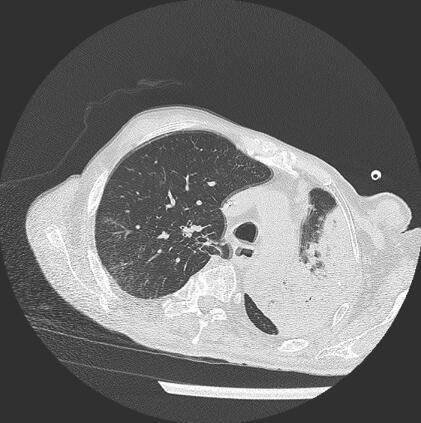

诊疗经过:患者入院后经验性应用拉氧头孢2g,每日2次抗感染,间断后鼻道吸痰,予吸氧、雾化、祛痰、平喘、补液等常规治疗。患者体温进行性下降,6月22日痰培养回报铜绿假单胞菌,对头孢菌素、喹喏酮类、碳氢霉烯类抗生素敏感。因对头孢吡肟定量结果≤2,改用头孢吡肟2g,每日2次;尿培养示酵母样真菌,加用氟康唑0.4g,每日1次,碳酸氢钠膀胱冲洗每日2次。患者体温波动在37~38℃,6月27日患者突发高热,体温39.1℃,血压下降,予多巴胺5~10μg/(kg·min),当日痰培养回报铜绿假单胞菌及鲍曼/溶血不动杆菌。铜绿假单胞菌药敏同前,鲍曼不动杆菌仅对头孢哌酮-舒巴坦钠敏感,对左氧氟沙星及亚胺培南中介,余均耐药,尿培养阴性。胸CT示双肺感染,左侧胸腔积液。

图4 2011年6月28日胸CT